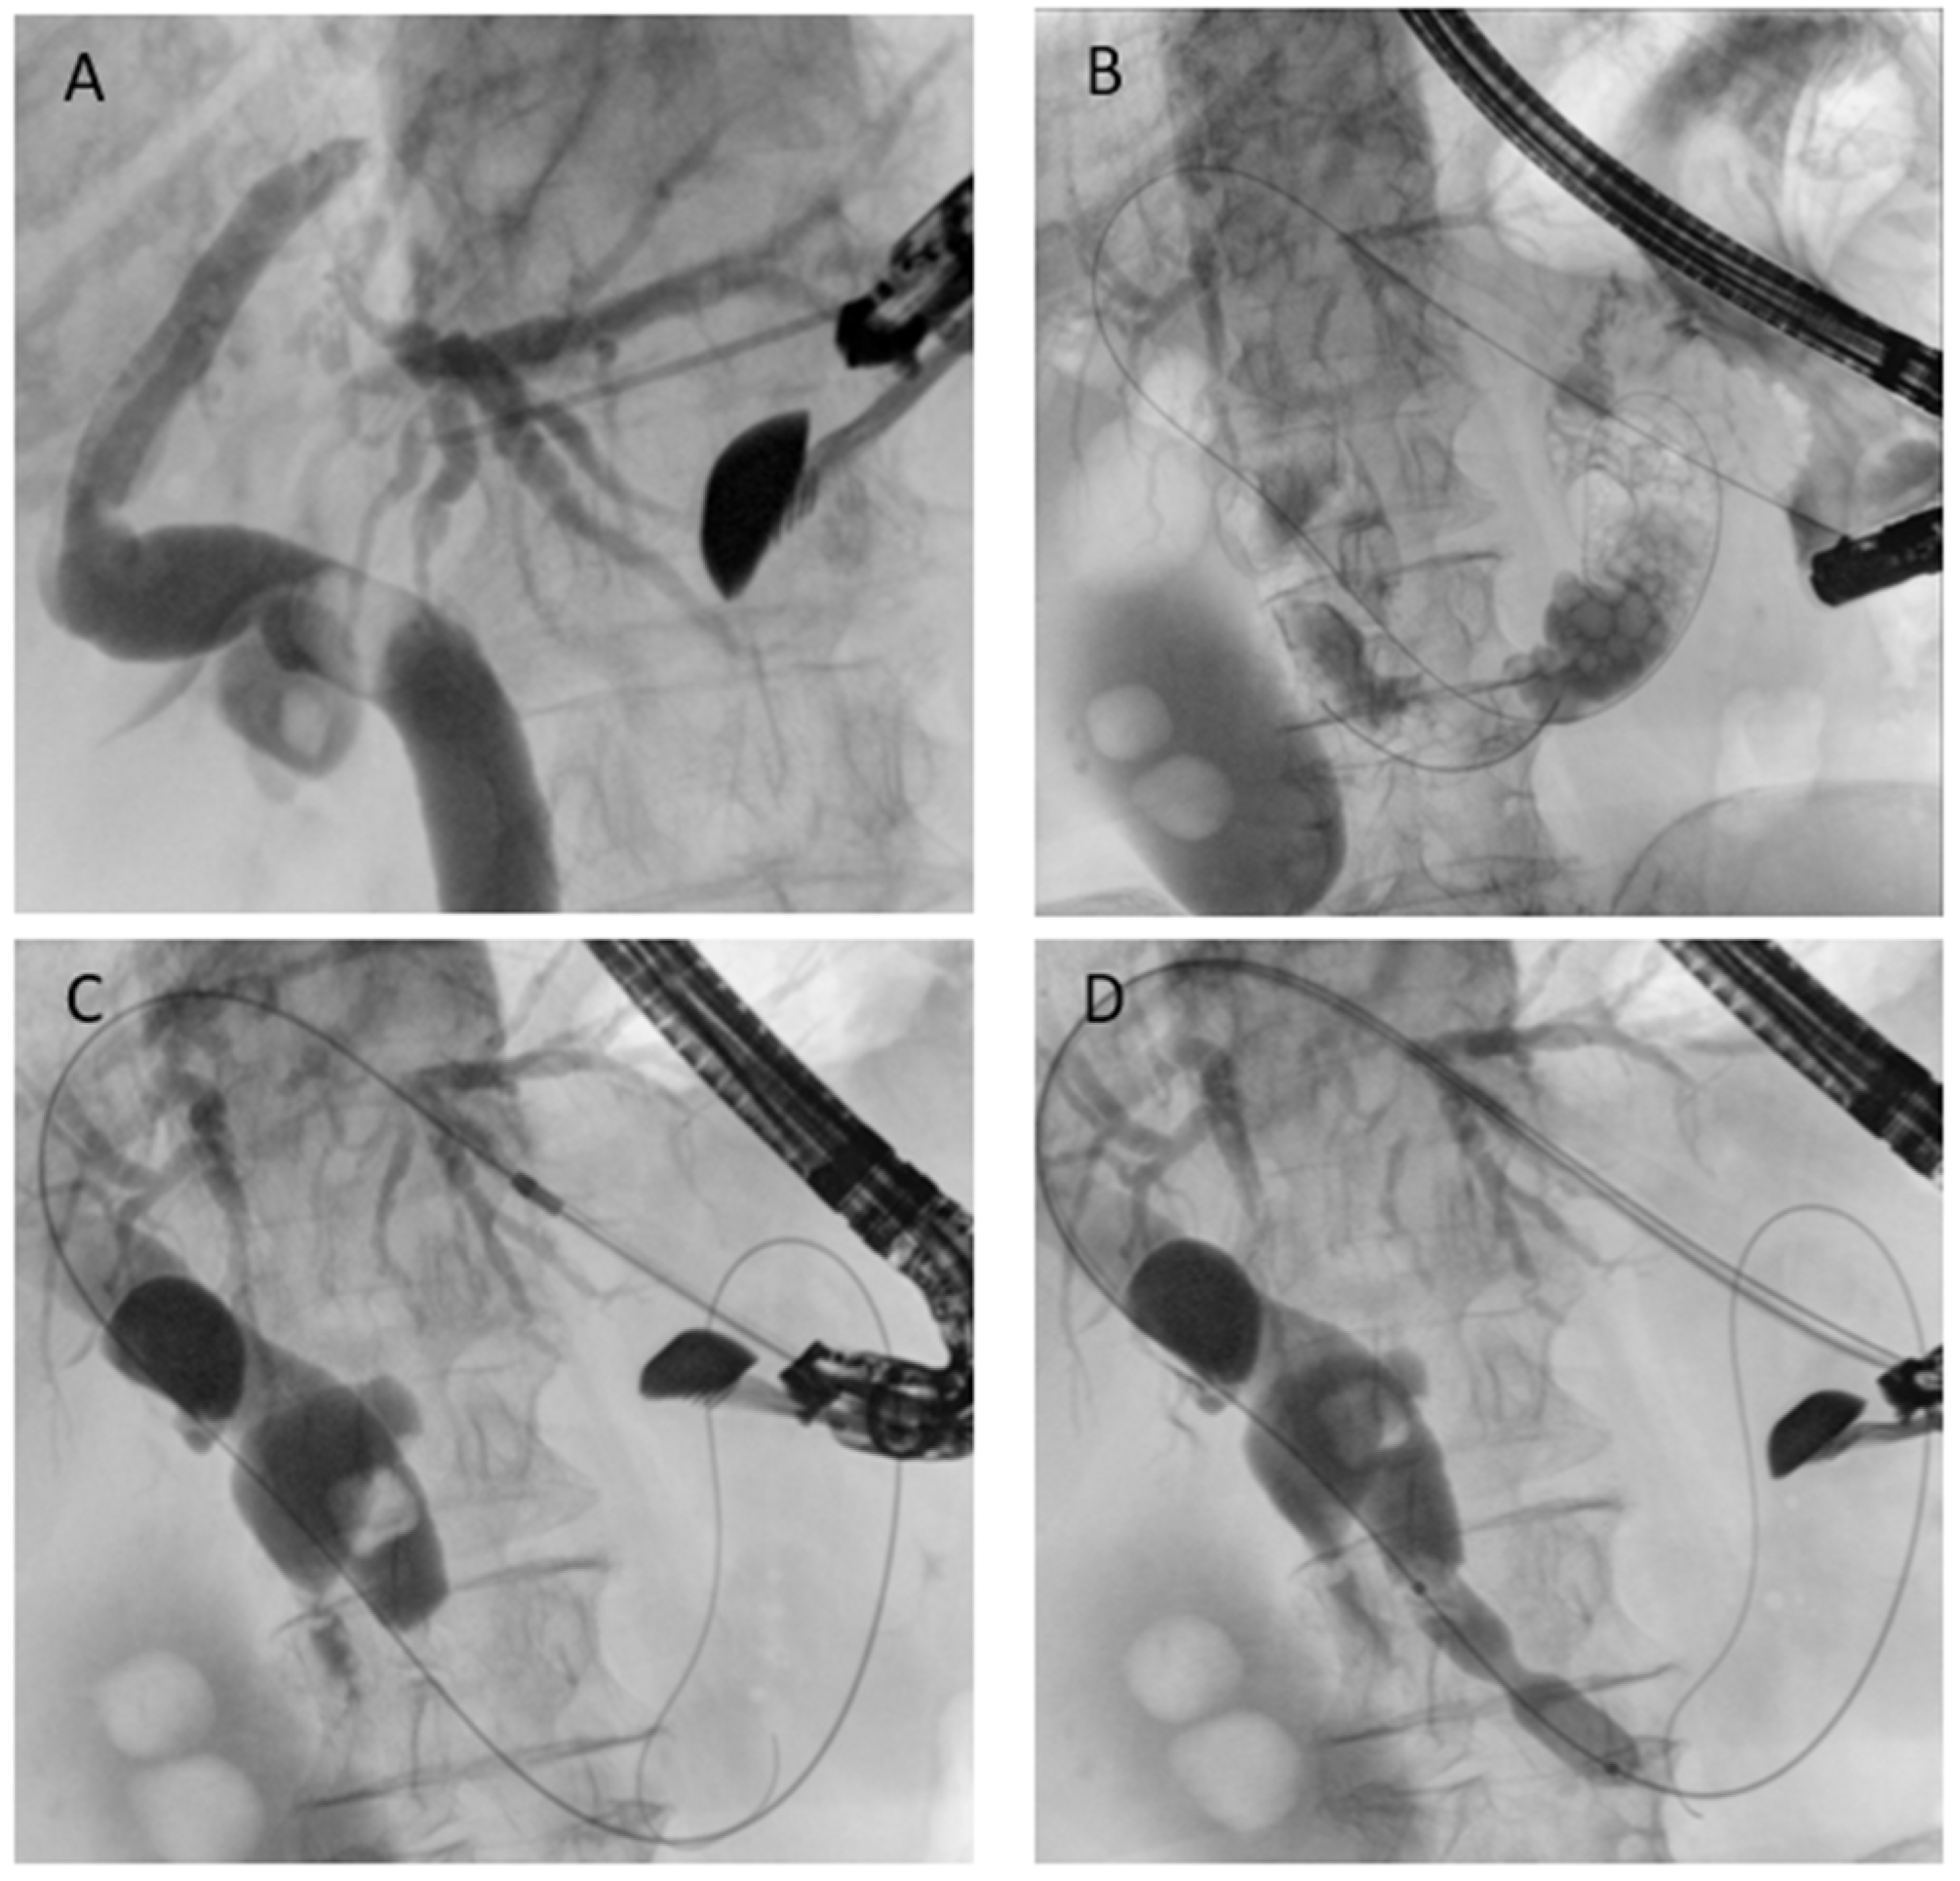

5.3.2. EUS-Guided Antegrade Drainage

EUS-guided antegrade drainage is conceptually similar to interventional radiology: the technique involves puncture of a biliary duct, usually from the stomach, using a large caliber needle (usually 19- or 20-Gauge needle), guidewire passage into the biliary tree and, through the papilla/anastomosis, into the downstream bowel (Figure 7). The endoscopist can perform a dilation if necessary and remove biliary stones when present or place a self-expandable metal stent. Technical success rates above 85–90% and clinical success of around 80–90% have been reported. AEs occur in 10–15%, mostly bile leakage or cholangitis [44]. The main advantage of antegrade stenting is that it preserves a physiologic drainage route and avoids external catheters, while the drawback is that reintervention can be technically challenging once the stent is in place. Generally, there is no need to place a stent to protect the initial needle access [45].

Figure 7. EUS-guided antegrade drainage. (A) Puncture of the intrahepatic duct; (B) guidewire passage into the biliary tree and across the papilla; (C) dilation of the gastric access using a cystotome; (D) endoscopic papillary dilation performed with a biliary balloon dilatation catheter.